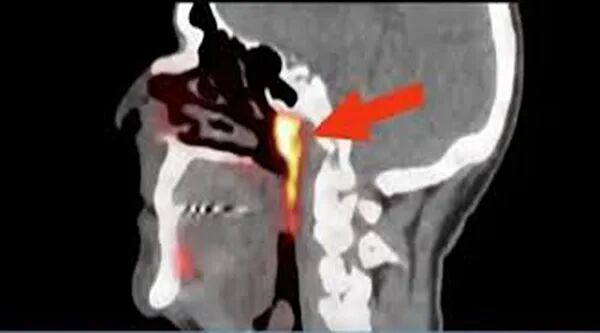

由于新器官位于鼻子后面一块被称为“咽鼓管隆凸”的软骨之上,因此研究人员将其命名为“咽鼓管唾液腺”。他们表示,人体鼻腔和口腔后面的上咽喉部得以润滑或湿润,靠的也许就是它。研究共同作者、荷兰癌症研究所放射肿瘤学家沃特·福格尔在一项声明中说,除人类已知分别位于舌头下方、下颚下方及后方的三个大的唾液腺,咽喉和口腔黏膜组织内还可能散布着上千个极小的唾液腺。然而,最新发现的“咽鼓管唾液腺”,之前从未被做过任何记录。解剖学迄今已有百年历史,而时至今日,还能发现人类器官家族新成员,这让研究人员们惊讶不已。有意思的是,这个新器官的发现极为偶然,它是研究人员在借助新技术研究前列腺癌时意外看到的。

刚发现时,没有任何研究人员敢相信自己的眼睛。为证实这一最新发现,福格尔团队对100名参与该前列腺癌研究的患者(其中99人为男性)全部进行了仔细扫描,发现“所有人都有这一腺体”。

他们立刻对两具捐赠尸体的鼻咽部进行了实体解剖,发现“该新器官由黏膜腺组织和流入鼻咽部的导管构成”。“研究人员研究了在格罗宁根大学医学中心接受治疗的700多名癌症患者的医疗档案后发现,患者这一腺体部位受到的辐射越多,他们在治疗中报告的副作用就越多——由于之前没人知道这一咽鼓管唾液腺的存在,所以也没人试图去避免照射这一部位。”“今后,在头部和颈部使用放射性疗法治疗癌症的医生可以设法避免照射这一唾液腺,因为破坏这些腺体可能会影响到患者的生活质量——该新器官的发现可能会从此避免以往癌症患者在治疗后进食、吞咽或说话时遇到的麻烦。”福格尔说:“接下来,我们将研究如何更好地保护这些新腺体,如果我们能做到这一点,患者可能会面临更少的副作用,这有益于提高患者治疗后的整体生活质量。”